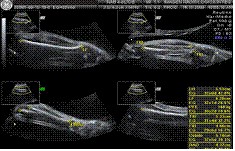

El estudio debe revisar la mayoría de las estructuras del producto y observar presencia o ausencia y asimetría de las estructuras, a decir:

En Cráneo la circunferencia cefálica y el diámetro biparietal.

En Cerebro las siguientes estructuras: ventrículos cerebrales, plexos coroides, línea media, cerebelo y cisterna magna y ventrículos laterales.

En Cuello pliegue nucal.

En Columna Vertebral integridad, espina bífida, tubo neural y escoliosis.

En Cara perfil, huesos nasales, labio superior de la boca y orbitas.

En Tórax el corazón (su anatomía), grandes vasos y pulmón incluyendo diafragma.

En Abdomen Estomago, riñones, vejiga, inserción del cordón umbilical en abdomen y numero de vasos, pared abdominal y circunferencia abdominal.

En extremidades brazos y piernas presencia y ausencia, medición de humero, cubito, radio y fémur con tibia y peroné, manos, pies, dedos y movimientos.